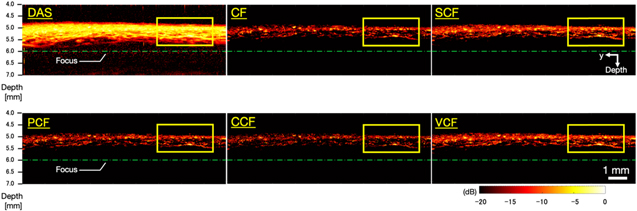

Figure 6 shows the B-mode images generated by imaging microvessels with each method applied. Figure 7 shows closeup images of the area enclosed by the yellow square in each B-mode image. In the image generated by the DAS method, the entire signal intensity was high, thus the vascular structure was unclear. On the other hand, the images generated by applying several types of coherence factors to the DAS method showed that the entire signal intensity was suppressed and the structure of the blood vessels could be clearly seen. However, in the image generated by applying the CCF method, the visualized vessel structure was partially discontinued (the white arrow in Fig. 7).

Fig. 6. (Color online) The B-mode images generated by imaging microvessels with each method applied.

Download figure:

Standard image High-resolution imageFig. 7. (Color online) Magnified images of the yellow square regions in the microvessels B-mode images (Fig. 6).

Download figure:

Standard image High-resolution imageFigure 8 shows the C-mode images of microvessels generated by each method. In the image generated by the DAS method, the running of the vessels was clear, but the vessels were visualized as being spread out. Table II shows the FWHM of the target vessel indicated by the blue line, the sharpening ratio by applying each coherence factor method to the DAS beamformed signals, and the CR and CNR calculated for each image. It could be seen that all types of coherence factors had the effect of sharpening the target vessel. In particular, the PCF method and the VCF method showed more than 20% sharpening effect and the CCF method showed 31% sharpening effect. However, in the image which applied the CF method, the CR decreased and the noise was emphasized compared to the other method. There was no significant change in the CNR between each type of coherence factor compared to the DAS method. The image obtained by applying the CCF method showed the highest CR and CNR, but the continuity of the vessels was partially lost, resulting in a rough image.

5.2. Microvascular imaging of human skin

In microvascular imaging of human skin, we qualitatively and quantitatively evaluated the effects of applying five coherence factors to improve the image quality by calculating the sharpening ratio, CR, and CNR. In the same way as the phantom study, it was confirmed that the five coherence factors had a sharpening effect on the target vessel in the C-mode MAP images. The CR increased in the four coherence factors applied images and suggested an improvement in image quality except for the CF.

Since the CF method quantifies the phase difference of the signal by the ratio of the coherent energy to the total energy of the received signal, the phase differences among the channel-domain signals were not considered accurately. In addition, each element of the annular array transducer used in this system had different sensitivity. Consequently, in the case of vascular imaging, the signal in both vessels and the background area was excessively suppressed, resulting in noise-enhanced images. Hence, the CF method was not suitable for our system.

The SCF method is a weighting function that binarizes the phase of the signal. The results of the phantom study indicated that the SCF method was effective in sharpening for B-mode images, but not effective in sharpening for C-mode images. The results in Sect. 4.2 showed that the SCF method improved the CR value of the images, suggesting that the method was effective for noise suppression against C-mode, but not for sharpening. In addition, the SCF method might cause local variations due to the phase binarization process, so that the PCF, CCF, and VCF methods were more advantageous for this system. Instead, the SCF method may be an effective method for devices that perform real-time imaging because the computational complexity of the SCF method is relatively lower than that of other coherence factors due to the phase binarization.

The CCF method had the highest effect of sharpening than the other methods in both phantom study and microvascular imaging, indicating that was the most sensitive method to phase differences. However, in the B-mode MAP images of the phantom study, the diameter of the phantom was thinner than 100 μm at all depths. Furthermore, in microvascular imaging of human skin, the continuity of the vessels was partially lost, resulting in a rough image. That was because even a small phase difference could cause excessive signal suppression in the CCF method for transducers with a small number of elements, such as the annular array transducer used in this system. In particular, in the case of microvascular imaging, the system was more influenced by the noise from the surrounding tissue, which might cause excess phase differences. 26,27) The CCF method might have a positive effect on multi-element transducers because of its high sensitivity in capturing the phase differences.

The results in Sects. 4.1 and 4.2 suggested that the PCF and VCF methods were effective methods for sharpening and noise suppression for our system. In a previous study, 18) the PCF method was reported to have no advantage over the CCF and the VCF methods as it assumes that the phase of the signal is between −π and +π, and a phase discontinuity near ±π may cause artifacts in the image. Nevertheless, such problem was not confirmed in our system performing MAP visualization, suggesting that both the PCF and the VCF methods were effective in suppressing noise components and clearly visualizing the vascular structure. In the future, it is necessary to evaluate the effects of the PCF and the VCF methods more precisely using a variety of in vivo data.